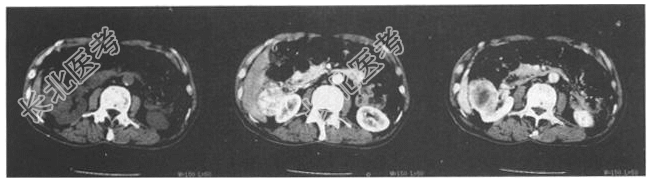

- 简答题2、CT检查所示如下图,诊断为?